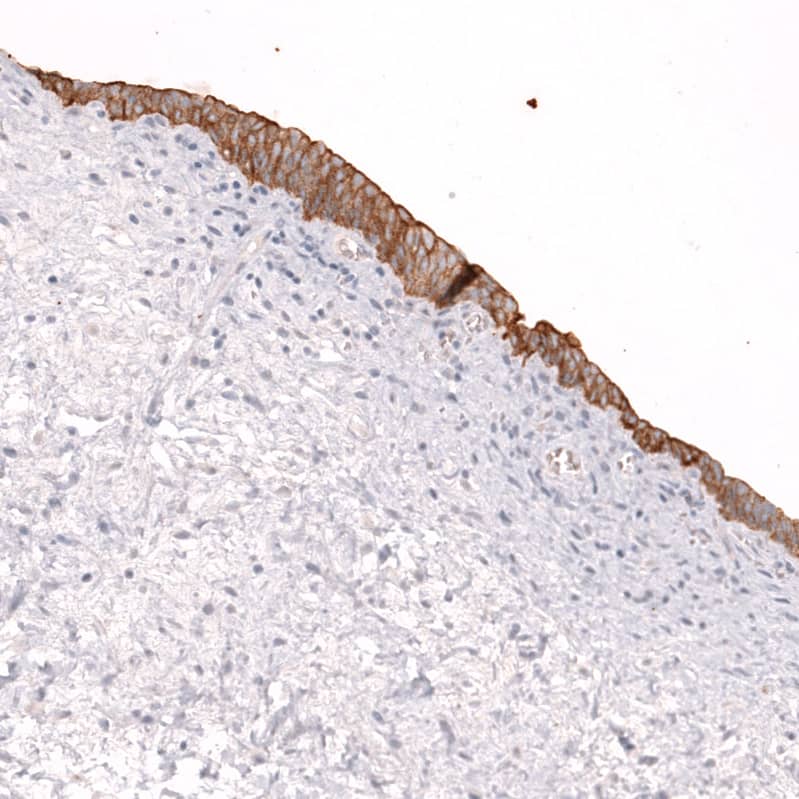

Staining of human urinary bladder shows moderate membranous positivity in urothelial cells.